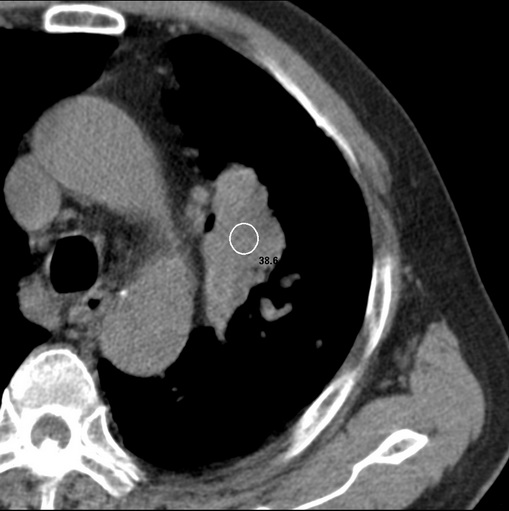

男性患者 81岁 咳嗽 咳痰 咯血

肿块贴近左肺门,包绕左上肺动脉,形态不规则。肿块增强扫描中度强化。纵膈内主动脉弓左旁间隙、气管隆突前、下间隙见多枚淋巴结影。综上考虑左侧中央型肺癌可能性大。图片没有完整上传,尤其是左肺上叶支气管分支层面没有上传,因此不好判断是叶支气管中断还是段支气管中断。另外,下图红色部分所示是“黏液支气管征”吗?